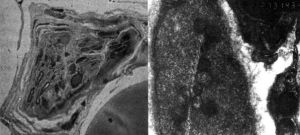

神經軸索球樣體INAD是由PLA2G6基因的突變(22q13.1)引起的,基因突變會導致磷脂代謝的改變和鐵在基底神經節的異常沉積